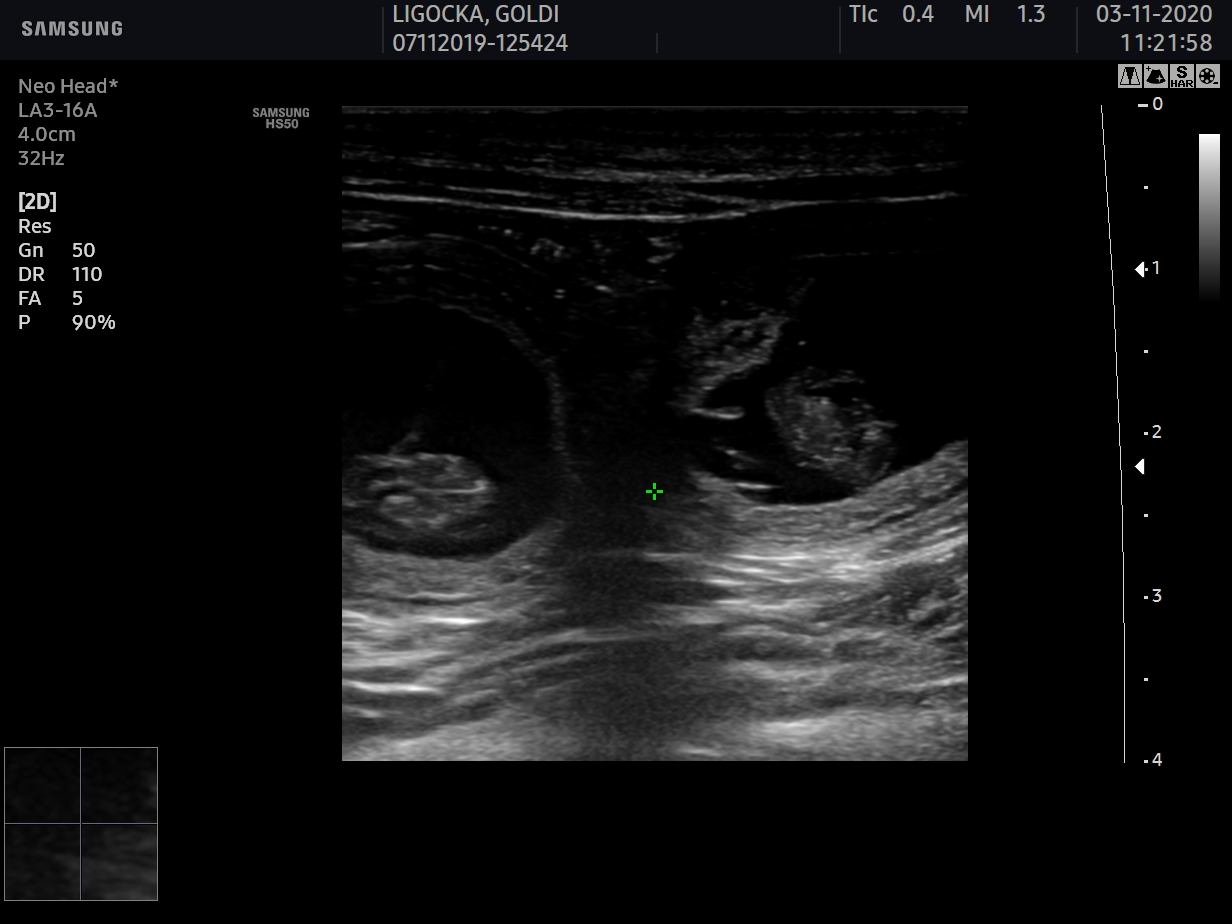

W tej chwili możemy już potwierdzić, że Goldi jest w ciąży i czekamy na narodziny szczeniąt około połowy listopada.

usg

W pierwszej połowie grudnia spodziewamy się rudo-białych szczeniąt w naszej hodowli.

To dla nas długo wyczekiwany i wyjątkowy miot.